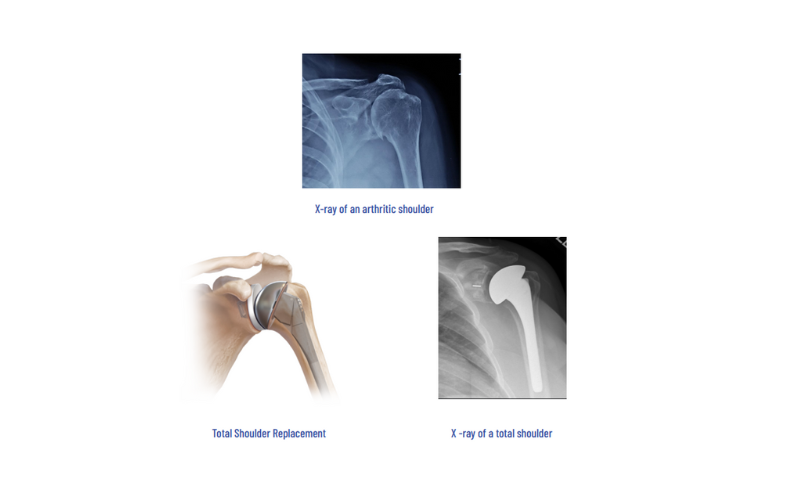

Total Shoulder Arthroplasty

In this procedure, the head is replaced with a metallic ball with a stem, which is fixed in the humeral stem. The worn out socket is resurfaced with a metal backed polyethylene insert. This procedure gives pain relief and functional improvement in advanced arthritis.